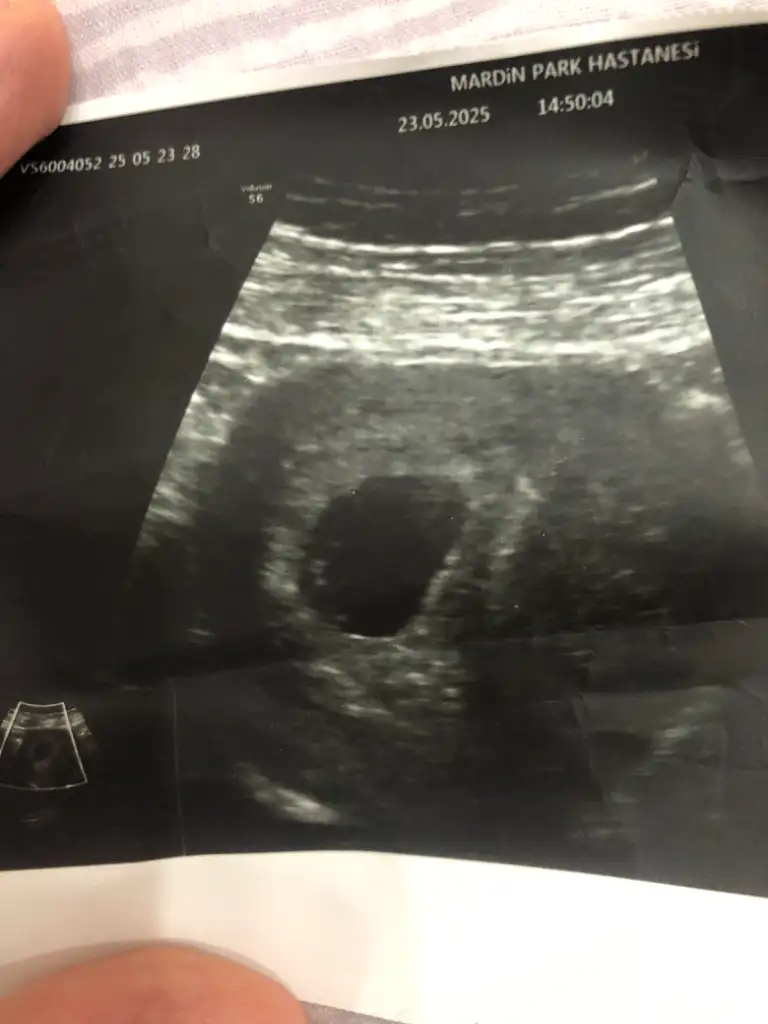

Kız gibi ama cinsiyetinin tam net görünmesi için en az 11 +12+13 haftaları bekle10+6 haftalık bebeğim. Ultrason fotoğrafından cinsiyet tahmini olan var mı acaba :) çok merak ediyorum tahminleriniz varsa yazar mısınız?Eki Görüntüle 3594321 Eki Görüntüle 3594322

10+6 haftalık bebeğim. Ultrason fotoğrafından cinsiyet tahmini olan var mı acaba :) çok merak ediyorum tahminleriniz varsa yazar mısınız?Eki Görüntüle 3594321 Eki Görüntüle 3594322